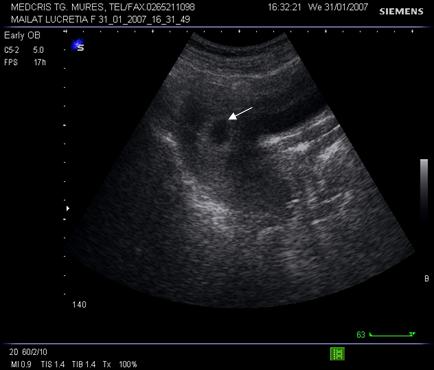

Fig. nr.11. Sac ovular intrauterin la o sarcina de 5 sapt., ecografia abdominla ( zona anecogena rotunda marcata cu sageata )